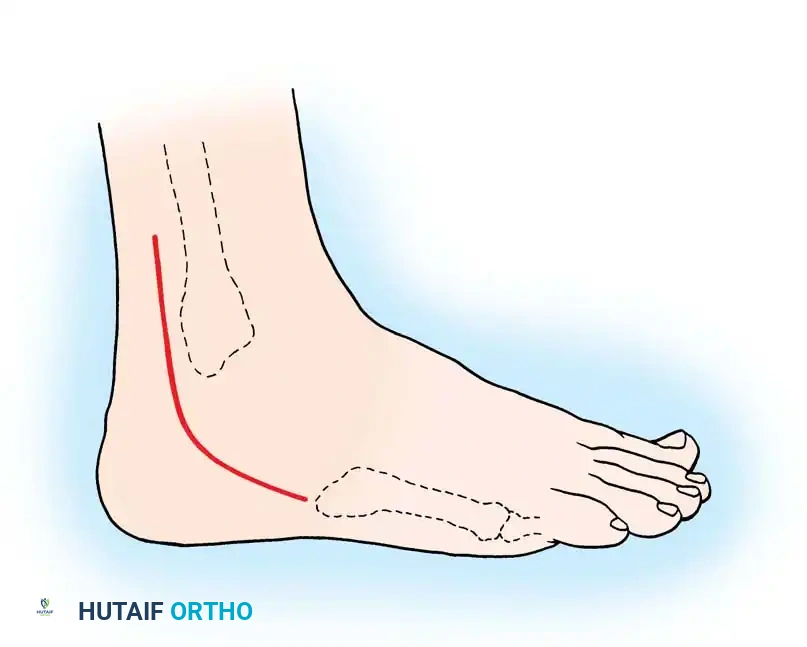

2. Surgical Approach

Begin the incision 10 to 12 cm proximal to the tip of the lateral malleolus, positioned approximately 1 cm posterior to the subcutaneous border of the fibula. Continue the incision distally and slightly obliquely to accommodate the bulbous posterior aspect of the lateral malleolus. Curve the incision gently 1 cm distal to the tip of the lateral malleolus, extending toward the base of the fifth metatarsal for another 3 to 4 cm.

Surgical Pitfall: The sural nerve and the small saphenous vein course just posterior to the peroneal tendons and are strictly subcutaneous at this level. Meticulous dissection is required to avoid iatrogenic neuroma formation, which can be more debilitating than the primary tendon pathology.